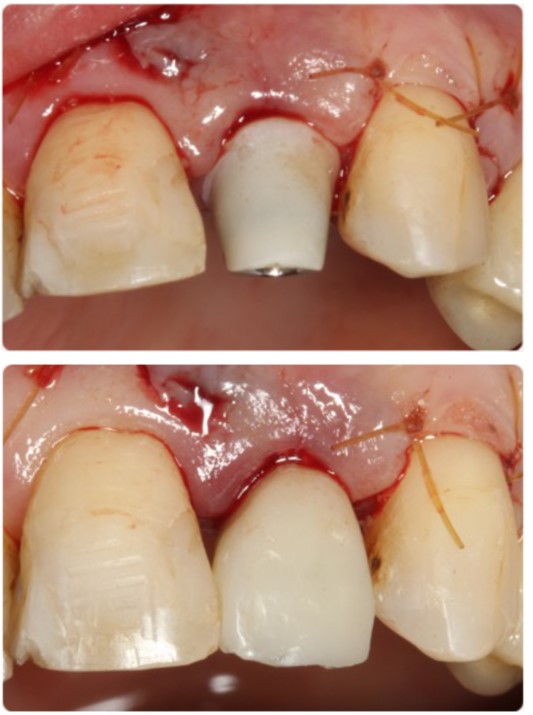

Pasul 6 – Procesul de instalare a pilonului de vindecare personalizat

Instalează bontul personalizat de vindecare în implant, utilizând șurubul de reținere disponibil împreună cu bontul temporar utilizat.

Instalează bontul personalizat de vindecare în implant, utilizând șurubul de reținere disponibil împreună cu bontul temporar utilizat.

Evaluează potrivirea clinică și radiografică adecvată cu implantul.

Umple orificiul de acces cu șurub cu un prim strat de bandă de teflon sterilă sau alt material adecvat.

Umple spațiul liber rămas al orificiului de acces cu șurub cu material compozit și fotopolimerizare.

Evacuează distanța ocluzală adecvată a bontului personalizat de vindecare și, dacă este necesar, reduce înălțimea acestuia.

Acest proces poate fi efectuat în momentul plasării implantului (protocolul cu o etapă) sau în stadiul descoperirii implantului.